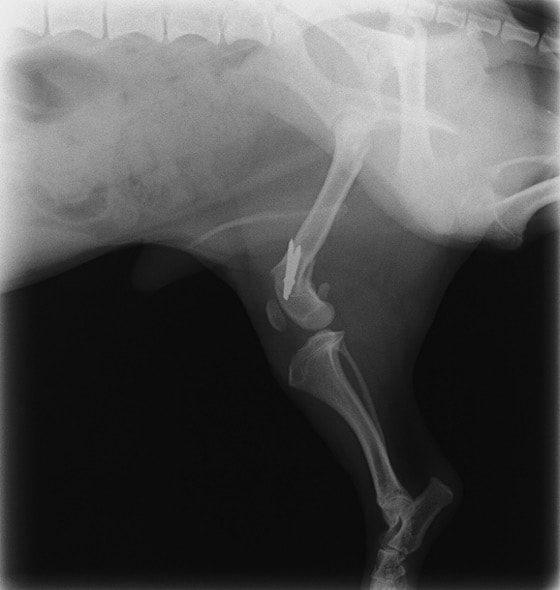

ペルシャ猫 11ヶ月齢 雄

他院にて左大腿骨遠位の成長板骨折(salter-harrisⅠ型)が認められており、治療相談を目的として来院。当院にて、キルシュナーワイヤーを用いたピンニングにより骨折部位の整復を行いました。術後の経過は良好で、現在も経過観察中です。

術前レントゲン